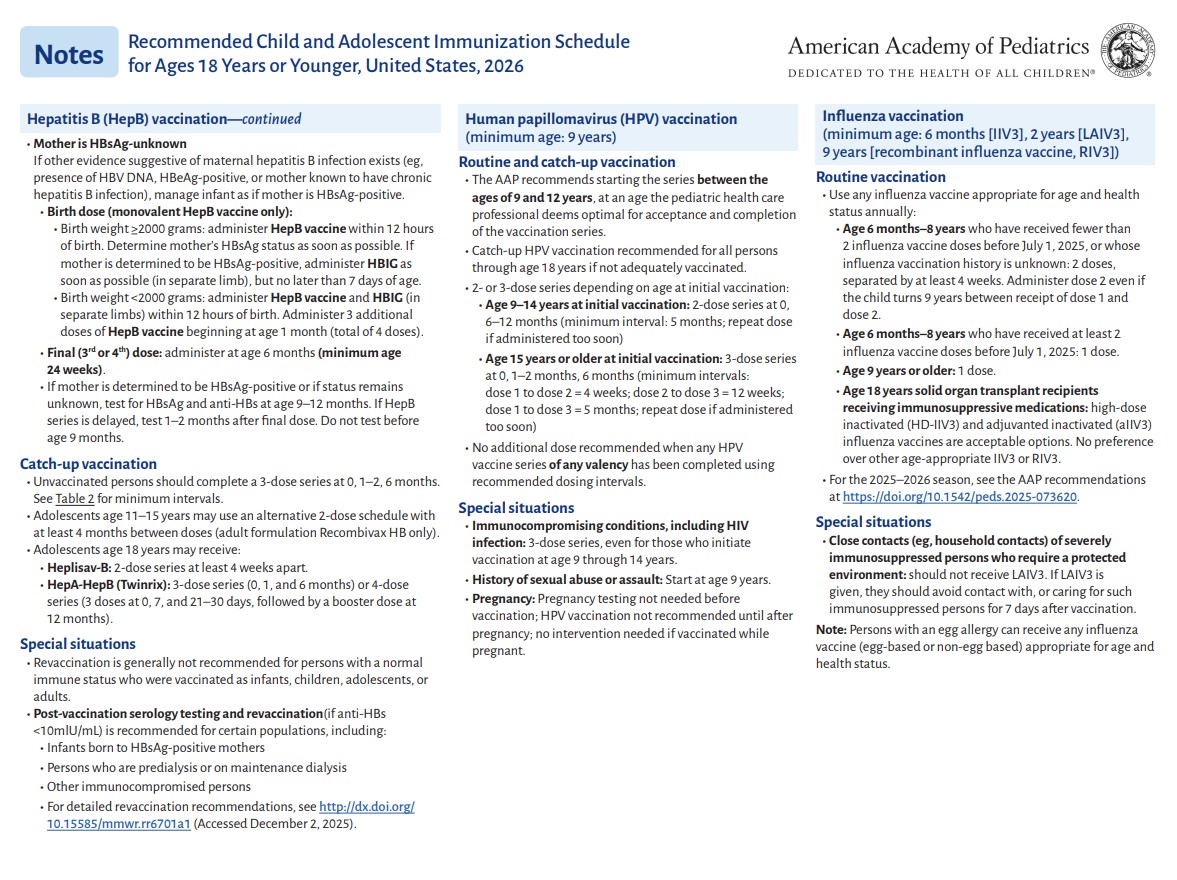

p 1

p 2

p 3

p 4